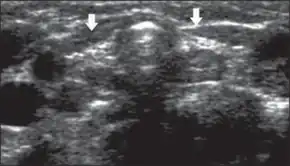

Ultrasonography thyroid gland arrows reduced dimensions, as well as increased echogenicity